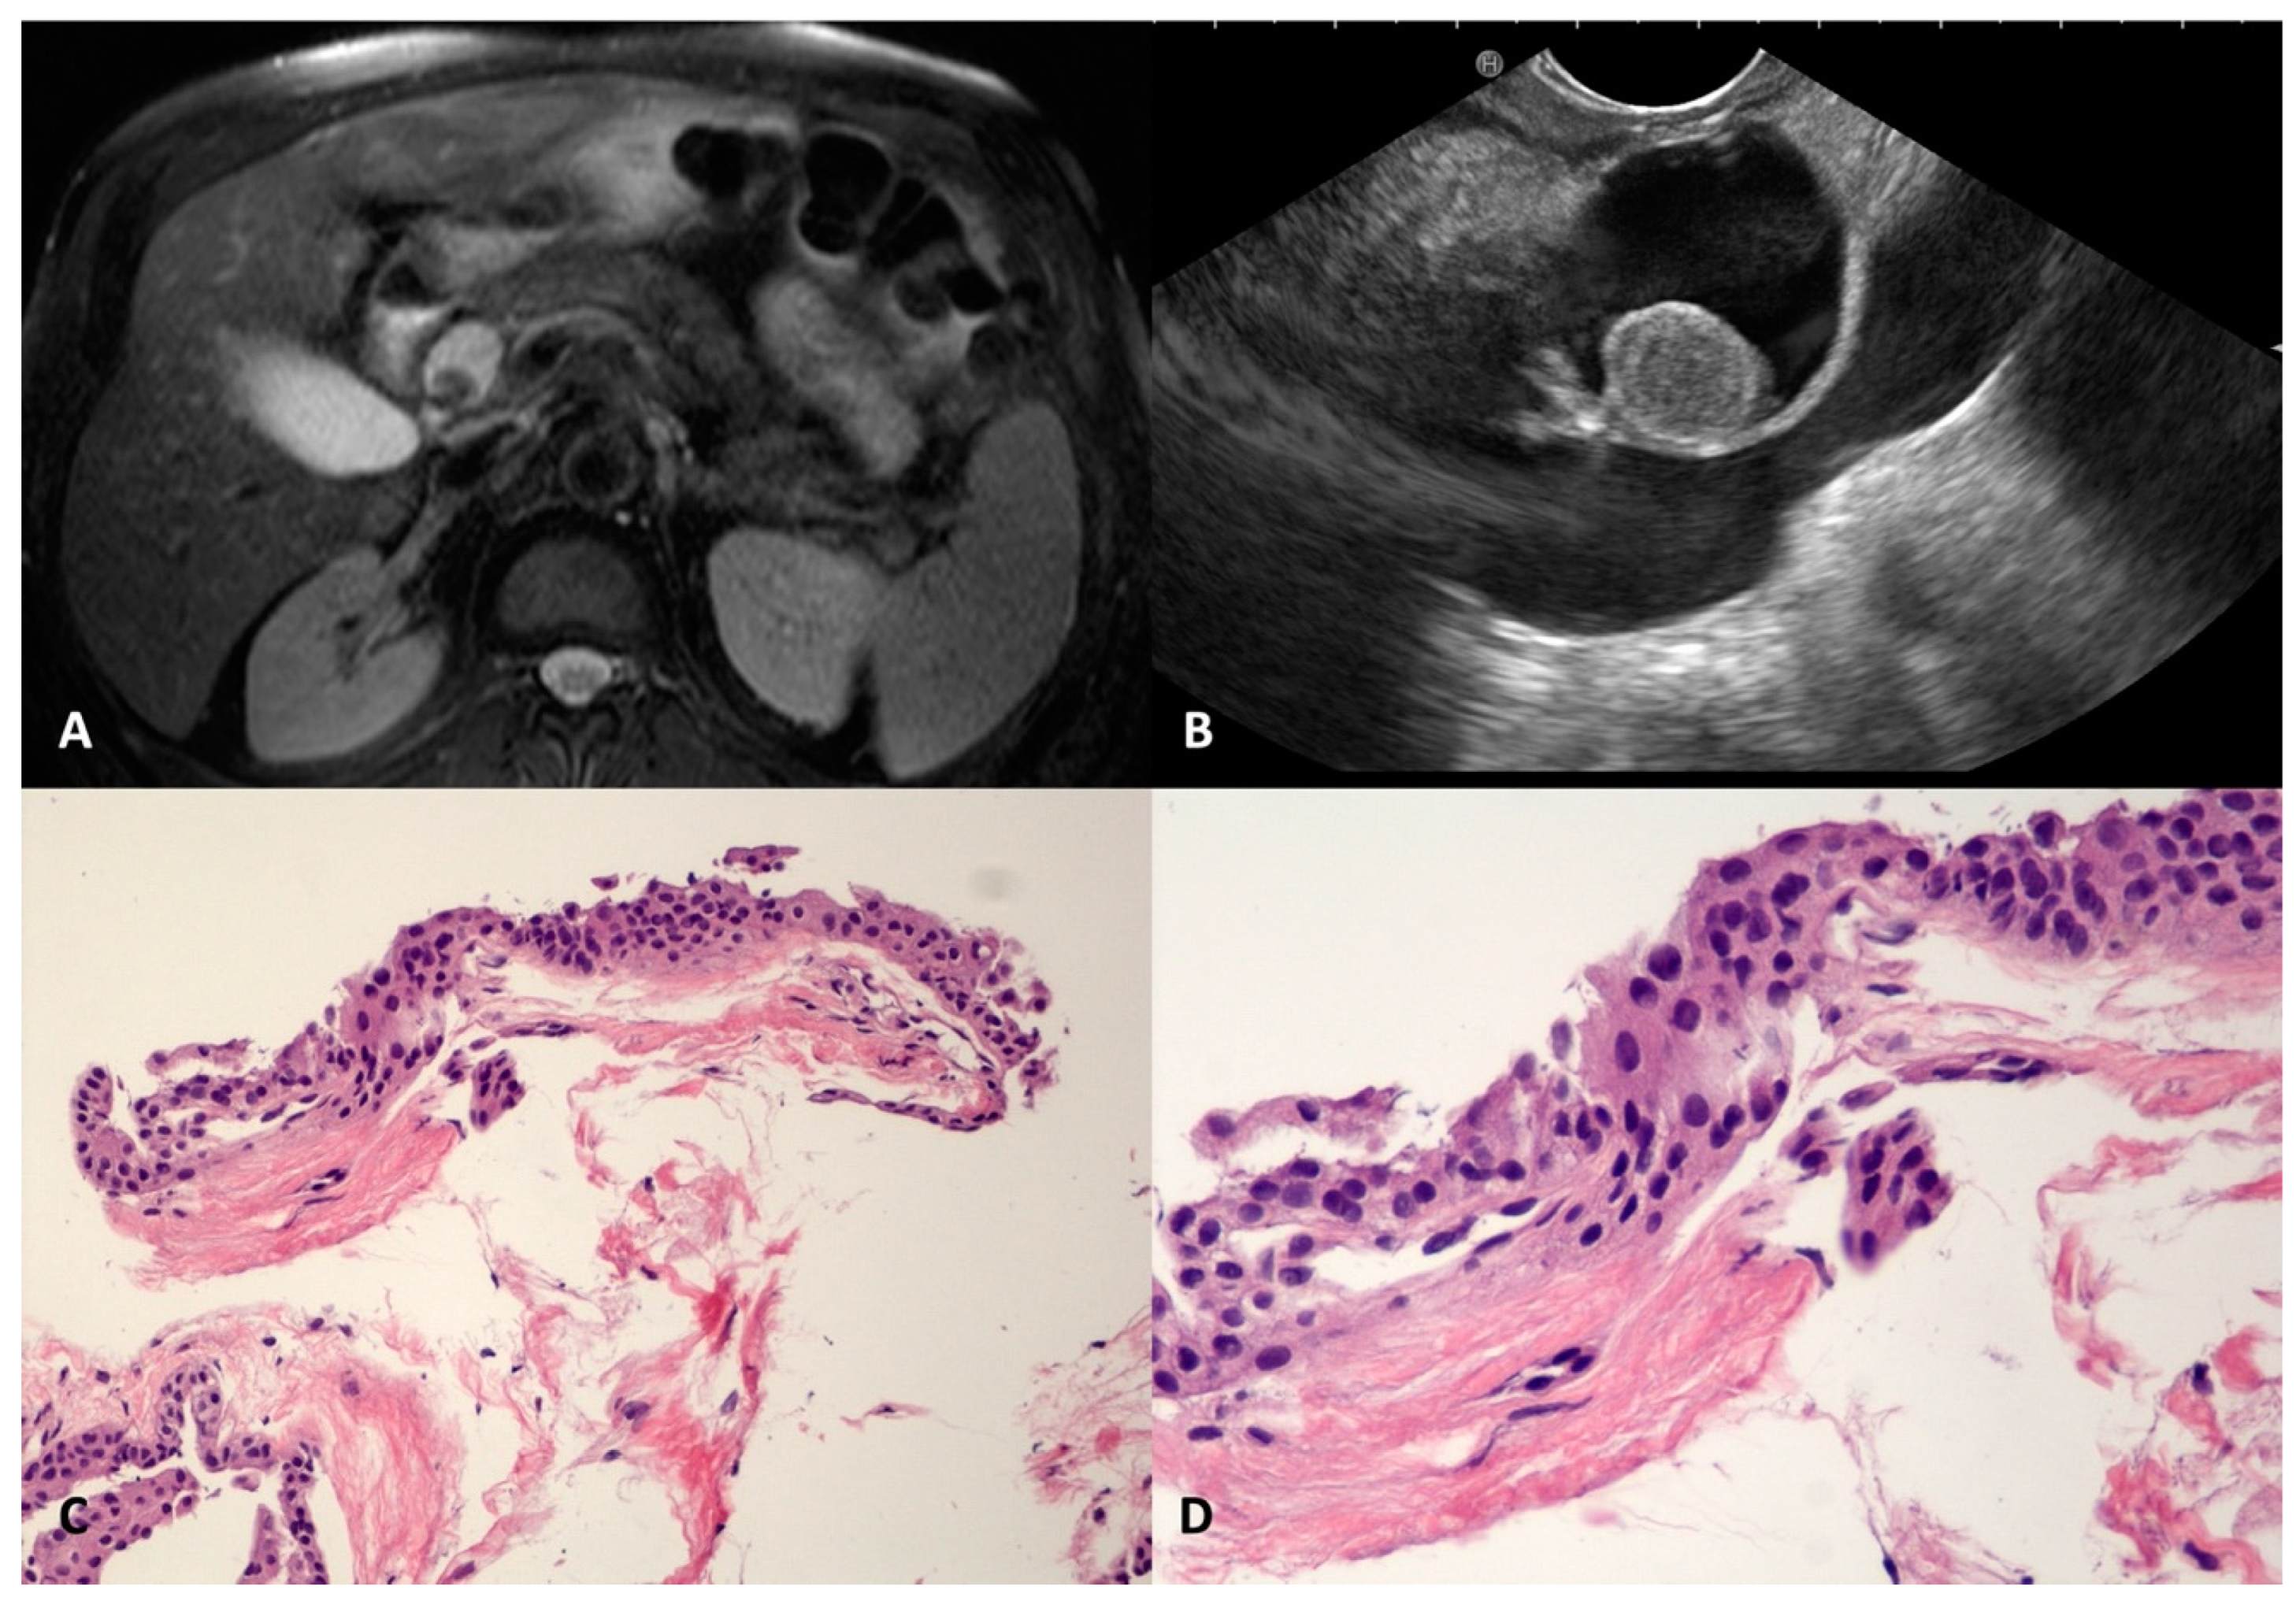

SCOP is a very rare benign pancreatic cyst that has been recently described; it is usually well defined and unilocular, probably due to the dilation of a branch-duct with metaplastic squamous transformation [,]. In our series, four SCOPs were found, three in the head (22, 22, and 32 mm) and one in the body (40 mm) of the pancreas. They were regular, had a thin and fibrotic wall, and had a homogeneous anechoic content, except in one case, where a round-shaped avascular intracystic nodule was documented in both magnetic resonance imaging (MRI) and EUS (Figure 3A,B). In two cases, the levels of CEAs were elevated in the cyst fluid cytology. The TTNB retrieved fragments of a simple stratified squamous epithelium, without keratinization, lining the thin fibrous cyst wall (Figure 3C,D).

Figure 3.

Squamoid cyst of pancreatic ducts. T2-weighted magnetic resonance imaging of a pancreatic cyst located in the head, with a nodule inside (A). The same cyst on an endoscopic ultrasound scan containing round vegetation that resulted in avascular at contrast-harmonic evaluation (B). The fibrous thin wall of the cyst is lined by stratified epithelium (C) without atypia and keratinization (D). Hematoxylin–eosin original magnification ×100 (C), ×200 (D).

SWNs originate from peripheral nerve sheath Schwann cells []. The pancreatic/peripancreatic localization of SWNs is extremely rare. Usually, SWNs arise from neighboring sites and secondarily involve the pancreatic gland, but more rarely can originate from pancreatic innervation []. SWNs are usually discovered incidentally as a painless mass in middle-aged patients. Malignant SWNs occur in 59% of patients with sporadic tumors []. SWNs are round or oval capsulated tumors with well-defined margins. Histologically, SWNs comprise two different areas: Antoni A and Antoni B. The first is composed of packed spindle-shaped cells that show immunohistochemistry positivity for protein S-100. The second area is occupied by hypocellular loose stroma and may be the subject of degenerative changes, such as cyst formation, hemorrhage, necrosis, and calcification. Cystic degeneration is related to larger sizes and mimics the whole spectrum of cystic pancreatic lesions. We observed one case of a large (103.5 mm) cystic unilocular SWN incidentally discovered on a transabdominal ultrasound and confirmed on a CT scan of a 40-year-old female (Figure 10A). According to the EUS, a unilocular cyst with a thickened irregular wall and corpuscolated fluid content was documented between the duodenal wall and the pancreatic head (Figure 10B). The TTNB specimens were composed of spindle cells with positive protein S-100 immunohistochemistry staining (Figure 10C–E). The lesion was subsequently surgically resected with confirmation of the diagnosis.

Figure 10.

Schwannoma. Computed tomography appearance of a large cystic lesion located between the second/third portion of the duodenum and the pancreatic head that appeared compressed and dislodged (A). On the endoscopic ultrasound, the lesion appeared as a round unilocular cyst with smooth borders and an irregular thickened wall (B). The whole mounted section of the cyst wall biopsy shows no epithelium lining the cyst (C). A well visible fascicle of spindle cells depicts the peripheral profile of the biopsy (D). Diffuse and intense immunolabelling for S100 in spindle cells (E). Hematoxylin–eosin original magnification ×40 (C), ×100 (D). S100 original magnification ×100 (E).